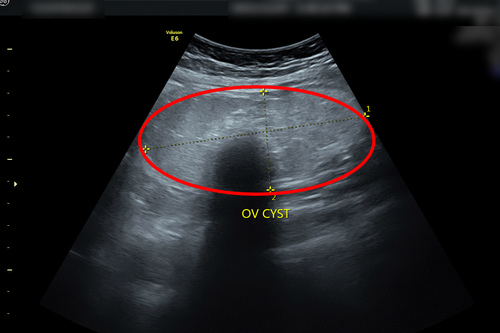

右圖:陳小姐卵巢瘤約10x5公分。